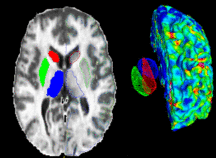

| PAR-07-249: R01AA016748 Measuring Alcohol and Stress Interaction with Structural and Perfusion MRI This project is funded under an NCBC collaboration grant to PIs James Daunais, Robert Kraft, and Chris Wyatt. The goal of this project is to examine the the effects of chronic alcohol self-administration on brain structure and function the monkey brain. MRI image analysis tools from the NA-MIC kit will be adapted for use with the monkey brain datasets. More... Funding Duration: 07/15/2009-03/31/2010 | |